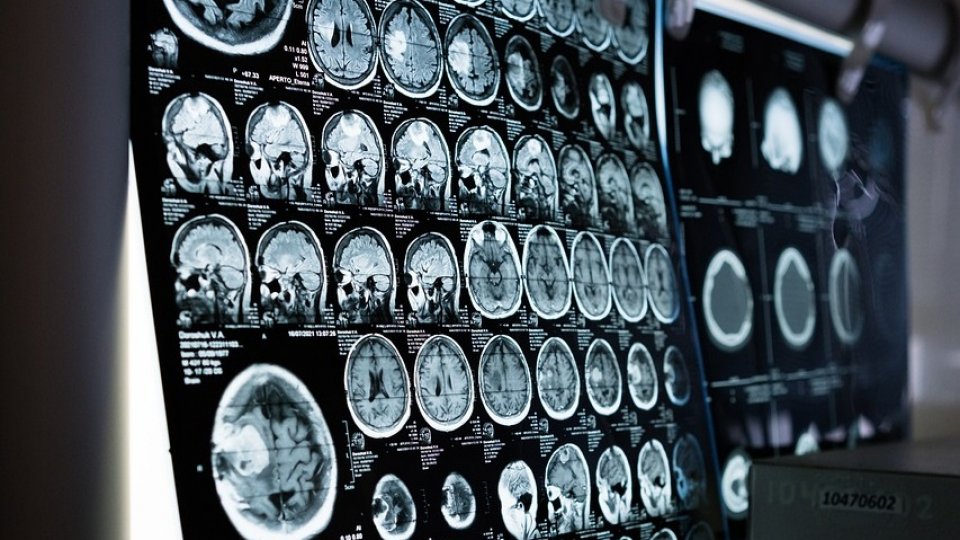

Ministrul Sănătăţii, Alexandru Rafila, a accentuat, luni, necesitatea dezvoltării la nivel naţional a unei reţele de centre de tratare a accidentului vascular cerebral, în condiţiile în care AVC-ul nu este doar o chestiune individuală, ci devine o problemă de sănătate publică.

'Ca să putem să tratăm cât mai eficient, iar eficienţa în cazul accidentului vascular cerebral se referă de cele mai multe ori la rapiditate, e clar că la nivel naţional trebuie să avem o reţea naţională de centre care să poată să facă acest lucru, să trateze cât mai repede pacienţii, fie prin tromboliză, dar mai ales printr-o pectomie, o manevră complicată care necesită o pregătire profesională specifică, realizată de radiologi intervenţionişti care nu sunt însă aşa de numeroşi încât să poată să facă funcţionale aceste centre 24 de ore din 24 în toată ţara', a explicat Rafila, care a participat la un eveniment dedicat luptei împotriva accidentului vascular cerebral găzduit de Universitatea de Medicină şi Farmacie 'Carol Davila'.